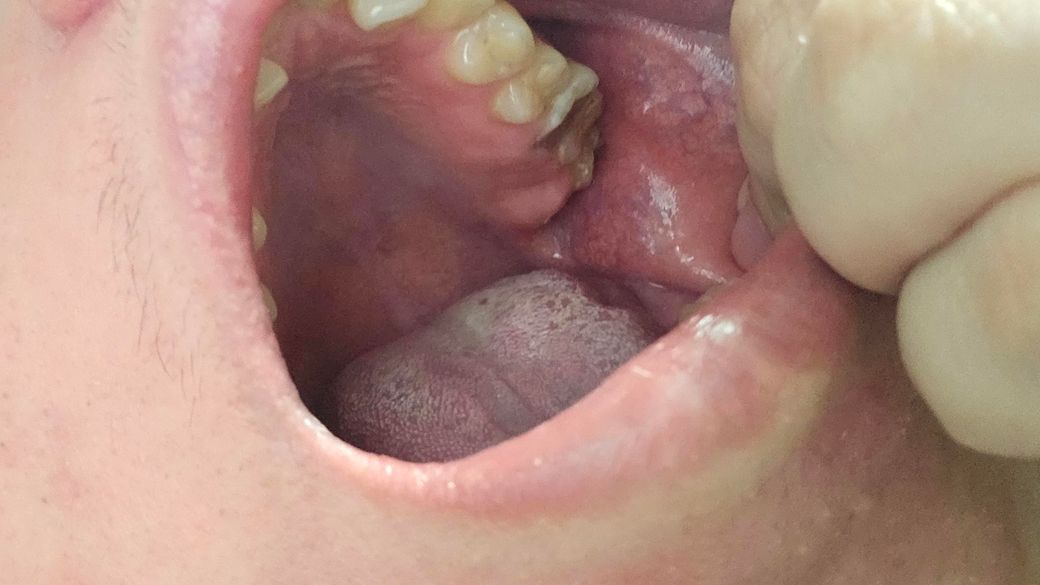

이상태 인데요 늦게갔도상관없나요

• 1번 째 사진

치료가 급한 치아이긴 합니다 이미 신경은 노출되었다고 봐도 되고 신경치료를 해야할 것 같습니다

다만 본인이 불편하지 않다면 7월에 가서 치료해도 됩니다 어차피 지금가나, 7월에 가나 신경치료 또는 발치입니다